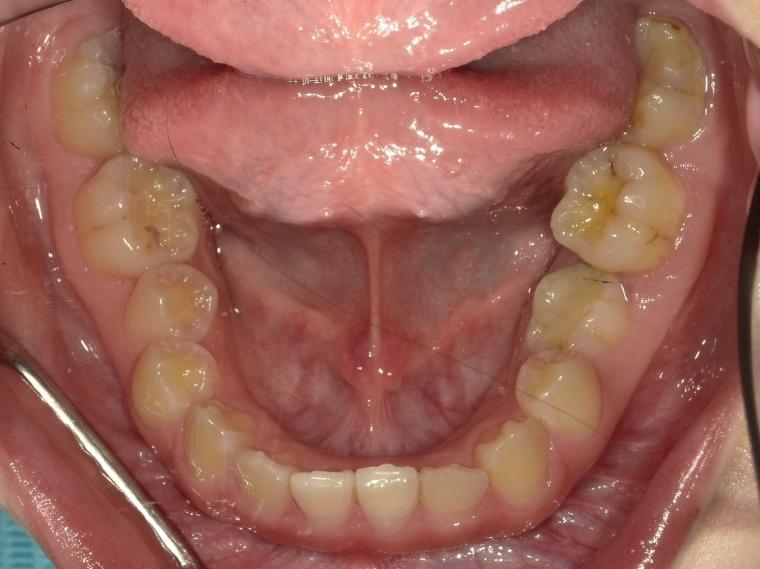

BEFORE

下顎第二小臼歯が先天性の欠損の患者さんです。

乳歯が生えていましたが、状態が悪くなり抜歯となりました。

他の歯の健康を考えマウスピース矯正で歯列を整えてからインプラントを1本埋込しました。